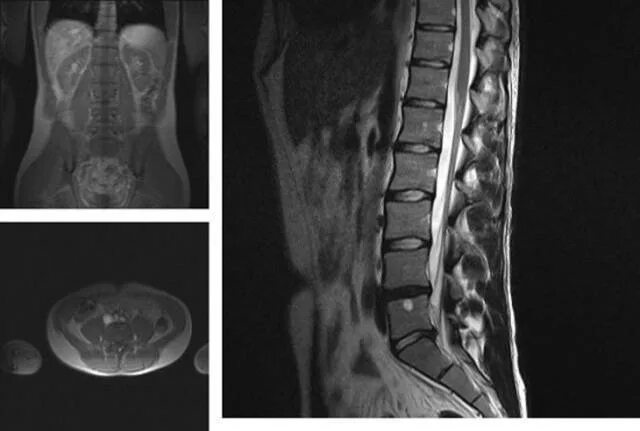

Спондилоартроз протрузии дисков спондилез